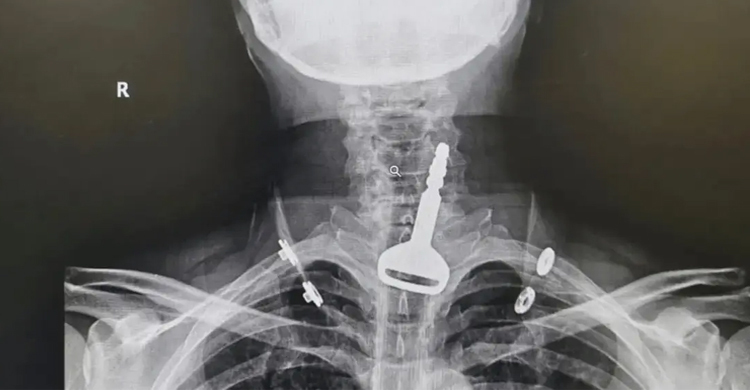

হাসপাতালে যাওয়ার পর ওই ব্যক্তির গলার একটি এক্সরেতে দেখা যায়, লোহার চাবিটি তার শ্বাসনালীতে আটকে আছে। ওই ব্যক্তির আগে থেকেই হার্টের সমস্যা ছিল। ফলে চিকিৎসকরা জরুরিভিত্তিতে অস্ত্রোপচারের সিদ্ধান্ত নেন। চিকিৎসকদলটি ১৫ মিনিট ধরে অস্ত্রোপচার করে ধাতব চাবিটি বের করে আনেন।